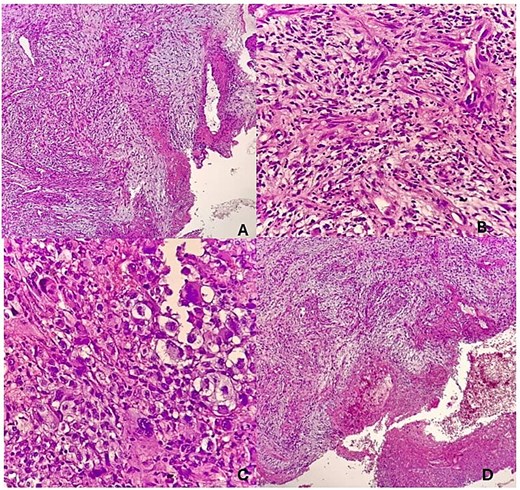

The patient was taken to the operating room for biopsy. Histological analysis demonstrated sections of tissue with an ulcerated squamous cell epithelium, having a false membrane and an acute on chronic inflammatory cellular infiltrate. The stroma had a fibromyxoid component with atypical spindle and fat cells with increased vascularization. Findings were consistent with a tumor with sarcomatoid differentiation and SSCC (Fig. 3). Immunohistochemical staining was advised for further tumor typing but was not performed due to financial constraints. The patient was subsequently lost to follow-up.

(A) Sections show tissue with an ulcerated squamous cell epithelium, having a false membrane and an acute on chronic inflammatory cellular infiltrate. (B) The stroma has a fibromyxoid component with aypical spindle and fat cells. (C) The cells are pleomorphic with prominent nucleoli. (D) There is increased vascularization.